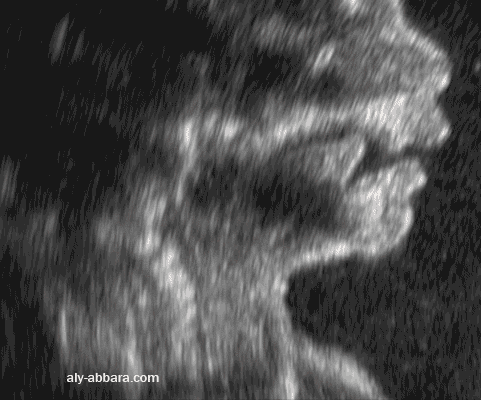

Coupe échographique sagittale médiane de la partie basse de la face fœtale ; il a été mis en évidence les éléments formant la bouche et la cavité buccale et leurs rapports anatomiques : lèvre supérieure et inférieure, maxillaire supérieur et inférieur et la langue fœtus âgé de 22 SA. |